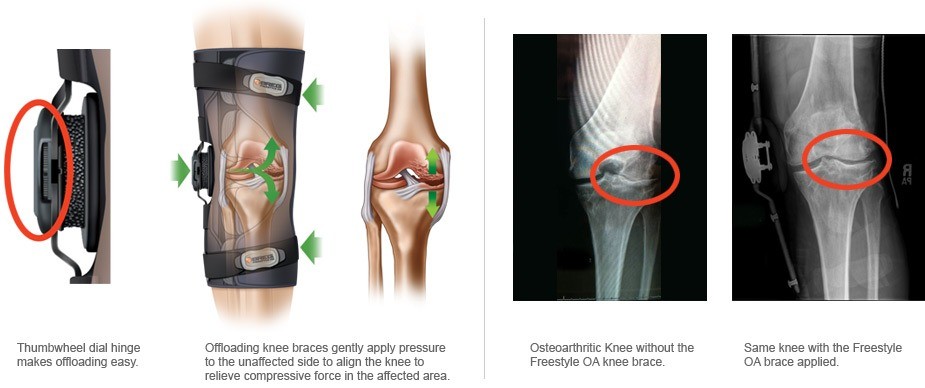

The Freestyle OA Knee Brace stands out as a revolutionary solution in the management of osteoarthritis. Engineered with cutting-edge technology and a patient-centric design, this brace offers a comprehensive approach to alleviate pain, improve joint stability, and empower individuals to lead more active lives.

One of the primary challenges faced by individuals with OA is managing chronic pain. The Freestyle OA Knee Brace addresses this issue through its innovative design, incorporating targeted compression to reduce pain and inflammation. By providing consistent and adjustable compression to the affected joint, the brace helps alleviate discomfort, allowing users to move with greater ease.

Joint stability is crucial for individuals with osteoarthritis, as it directly influences mobility and the ability to perform daily activities. The Freestyle OA Knee Brace excels in enhancing joint stability, providing crucial support to weakened or damaged areas. By promoting proper alignment and reducing unnecessary strain on the affected joint, the brace empowers users to move more freely and confidently.